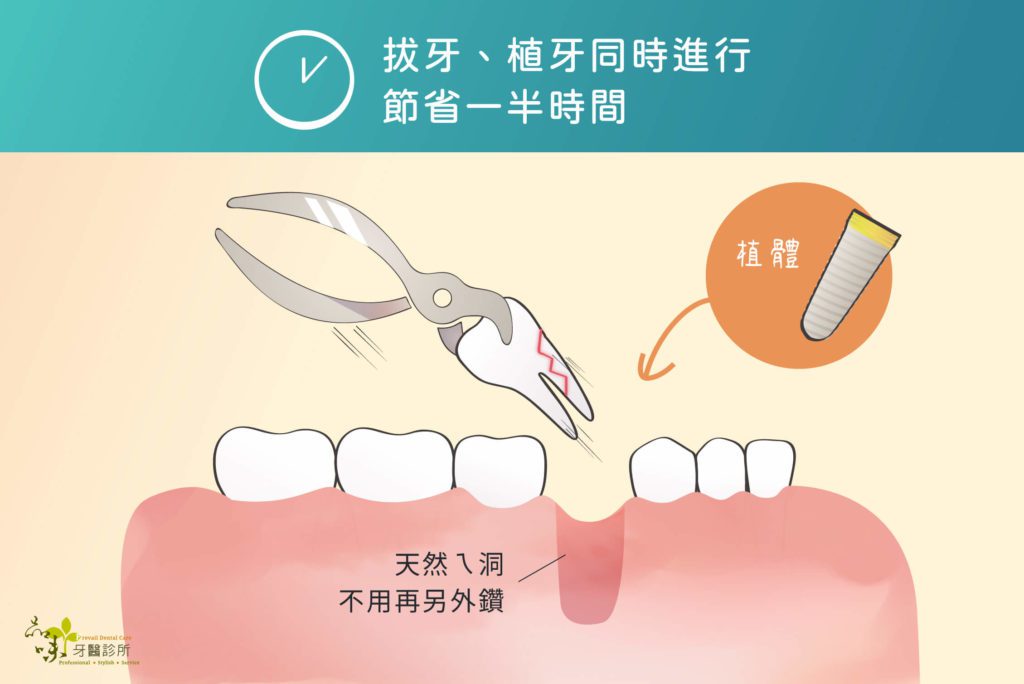

即拔即植,又稱為即拔即種或立即植牙(Immediate implant placement)。這種植牙方式的定義是:

「在牙齒拔除的當次診療中,醫師立即將植體植入乾淨的拔牙窩洞裡,讓拔牙傷口與植體一起癒合」

因為即拔即植是在拔牙當次施作,因此手術傷口比較小,並且不需切開牙齦。如此一來不但可以保存更多骨頭(齒槽骨)與牙肉組織,還能縮短植牙手術的時間,是微創植牙手術的一種。

相對地,即拔即植的療程時間可以縮短許多。醫師在當次門診施行多合一植牙手術,也就是當次門診就完成拔牙、植牙以及補骨手術。由於傷口癒合以及植體的骨整合時間可以同時進行,所以即拔即植的患者缺牙等待時間較短。